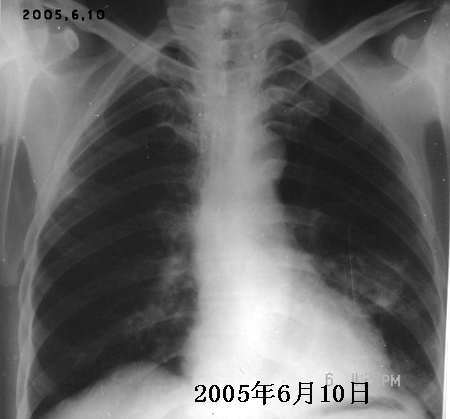

以下是引用jiajie在2005-11-6 22:07:00的发言:[br]1)左肺下叶阻塞性肺炎,胸腔积液,中心型肺癌可能大,建议纤支镜。[br]2)结合30年打石史,双肺弥漫性小结节考虑矽肺。

以下是引用sdqzwyx在2005-11-7 19:59:00的发言:[br]双肺弥漫大小不等的粟粒状结节影;肺纹理走行失去自然,粗细不均,边缘不规则,小叶间隔增厚;左上肺示不规则形致密影,从斑块边缘向周围伸出长短不一的致密索条影,临近的血管、支气管和叶间胸膜等结构受牵拉移位;左下肺示不规则团块状影,其内示空洞,洞内壁尚光整,左侧胸腔积液。右肺下叶背段亦示部分病灶融合。双肺可见局限性肺气肿。[br]诊断:结合病史符合三期矽肺表现(少数矽肺纤维斑块内可以形成空洞,一般认为是斑块中央感染引起坏死所致)但尘肺病人易合并肺结核,诊断可为三期+tb。所以此病人应进一步检查是否合并结核。